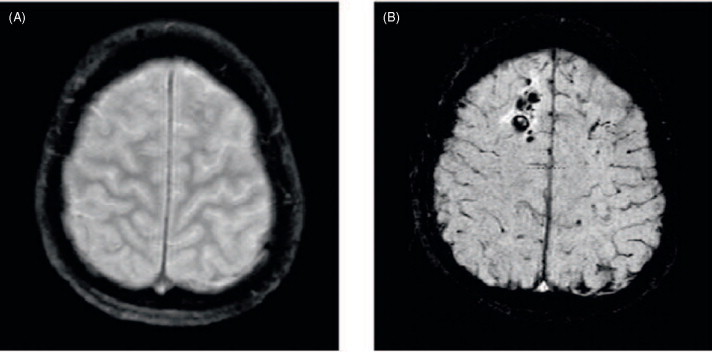

Sign of diffuse axonal injury on CT

“Blurring of white-gray junction”